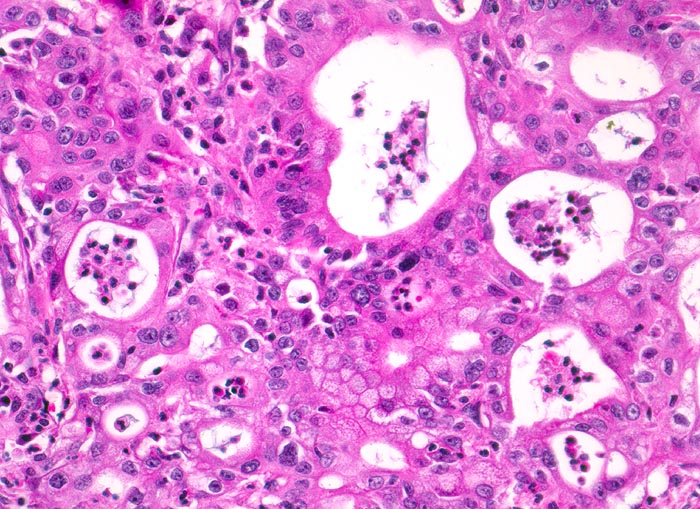

duktales Adenokarzinom des Pankreas

Maligne Tumordrüsen liegen dos à dos und bilden ein kribriformes (siebartiges) Muster. Die Zellkerne sind polymorph, das Chromatin ist vergröbert. Die Lumina der Tumordrüsen sind angefüllt mit neutrophilen Granulozyten.

Unscharf begrenzter weisser derber Herd im Pankreaskopfbereich. Stenosierung und praestenotische Dilatation von Ductus choledochus und Pankreasgang vor der Papille.

Zunehmender schmerzloser Ikterus. Sonographische Darstellung einer 4cm grossen echoarmen Raumforderung im Pankreaskopfbereich. Dilatation des Pankreasganges und des Ductus choledochus. Whipple Operation.

Histologie

200